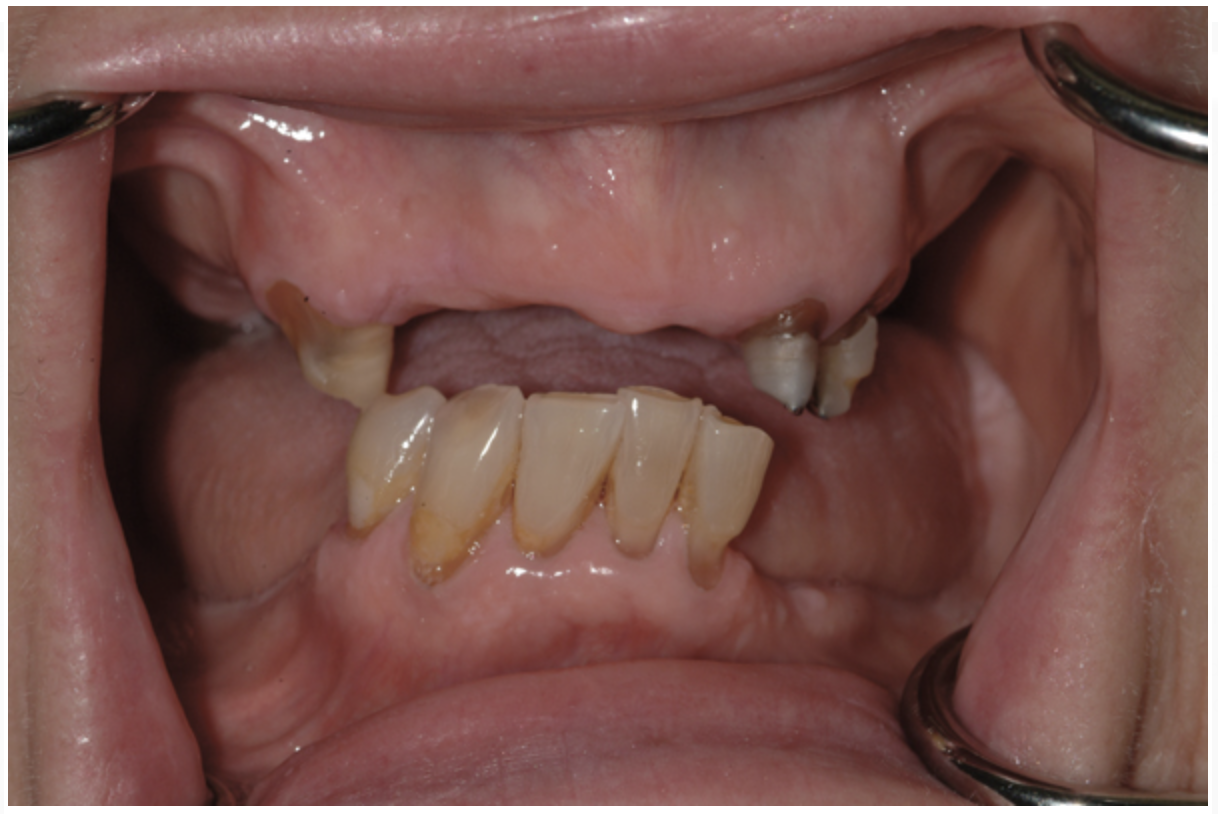

Dental rehabilitation with the All-on-4 treatment concept is often a life-changing event for edentulous and terminal dentition patients that results in unprecedented quality of life improvements (Figure 17 through Figure 20).

Fig 17. Pre-treatment smile of patient with terminal dentition.

Figure 17

Fig 18. The patient’s intraoral condition.

Figure 18

Fig 19. Patient smile shown 3 years post-treatment.

Figure 19

Fig 20. Patient intraoral condition 3 years following delivery of maxillary and mandibular All-on-4 definitive prosthesis.

Figure 20